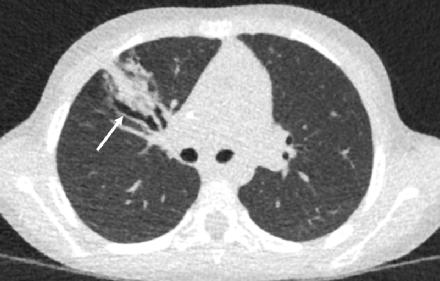

一些PCD-CT应用对儿科患者特别有利。较高的空间分辨率和对比噪声比提高了较小患者解剖结构的可见性,同时提高了剂量效率,有利于进一步降低剂量。使用PCD-CT的高分辨率模式,辐射剂量可以减少20%-30%,而不牺牲图像质量。此外,与某些常规EID CT系统中的使用类似,Tin滤波器可用于塑造多色X射线管能谱,去除低能光子,使更多的光子通过患者,并促进平扫诊断任务的剂量大幅降低。PCD-CT的这些特点使其成为各种儿科方案的理想选择,但超低剂量胸部CT是需要从年轻时开始重复成像检查的患者的理想应用,例如患有慢性气道疾病(如囊性纤维化)的年轻患者。图11显示了一名6岁囊性纤维化患者的平扫超低剂量CT图像,该图像在类似于胸片的辐射剂量下进行。

图11 在PCD-CT上扫描临床诊断为囊性纤维化的6岁女性(CT剂量指数:0.05mGy吸气[显示]和0.05mGy呼气)。PCD-CT显示右肺中叶圆柱形支气管扩张(箭头)。